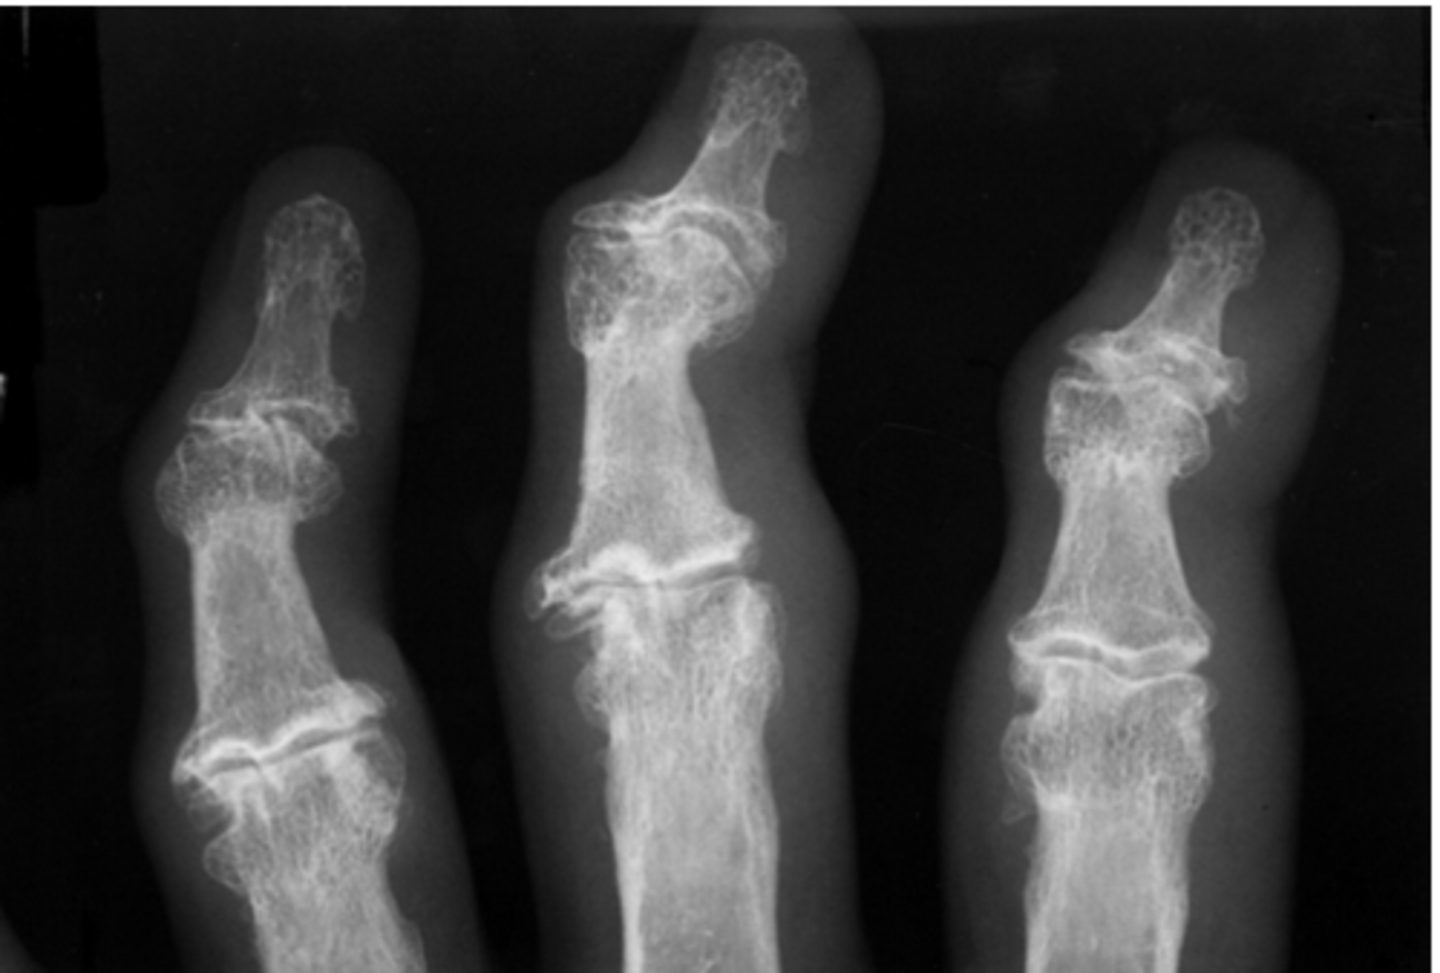

psoriatic arthritis

inflammatory arthritis associated with psoriasis, skin and nail changes along with joint changes, hands and feet usually

- juxtaarticular erosions

- enthesophytes -> bony proliferation at sites of tendon insertions

- pencil in cup deformity

- absence of osteoporosis